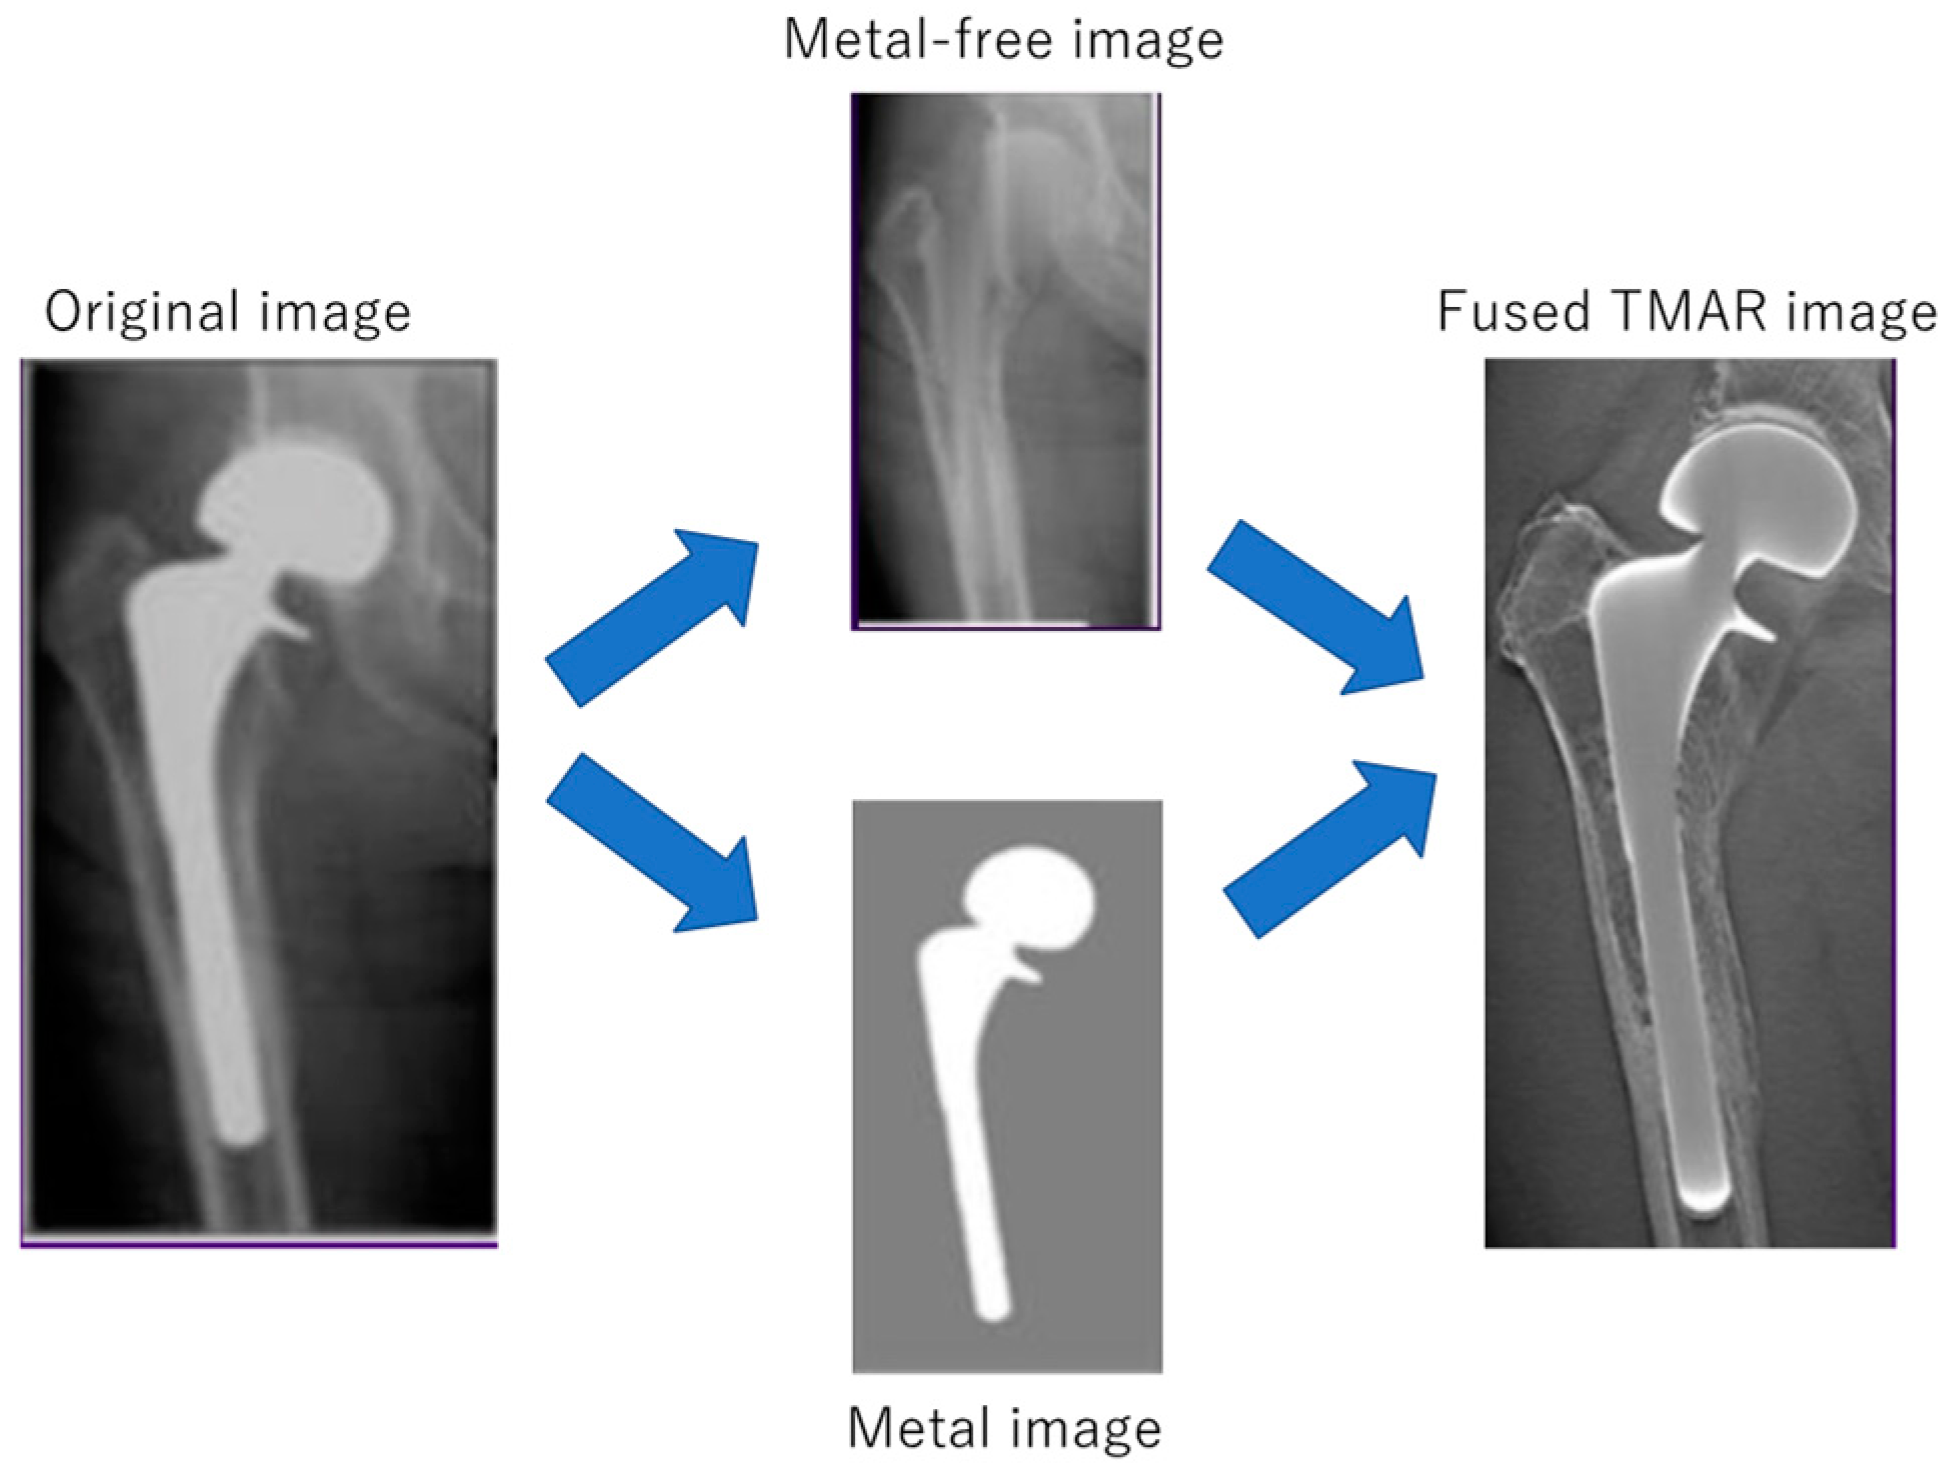

- Gomi, T.; Sakai, R.; Hara, H.; Watanabe, Y.; Mizukami, S. Usefulness of a Metal Artifact Reduction Algorithm in Digital Tomosynthesis Using a Combination of Hybrid Generative Adversarial Networks. Diagnostics 2021, 11, 1629. [Google Scholar] [CrossRef] [PubMed]